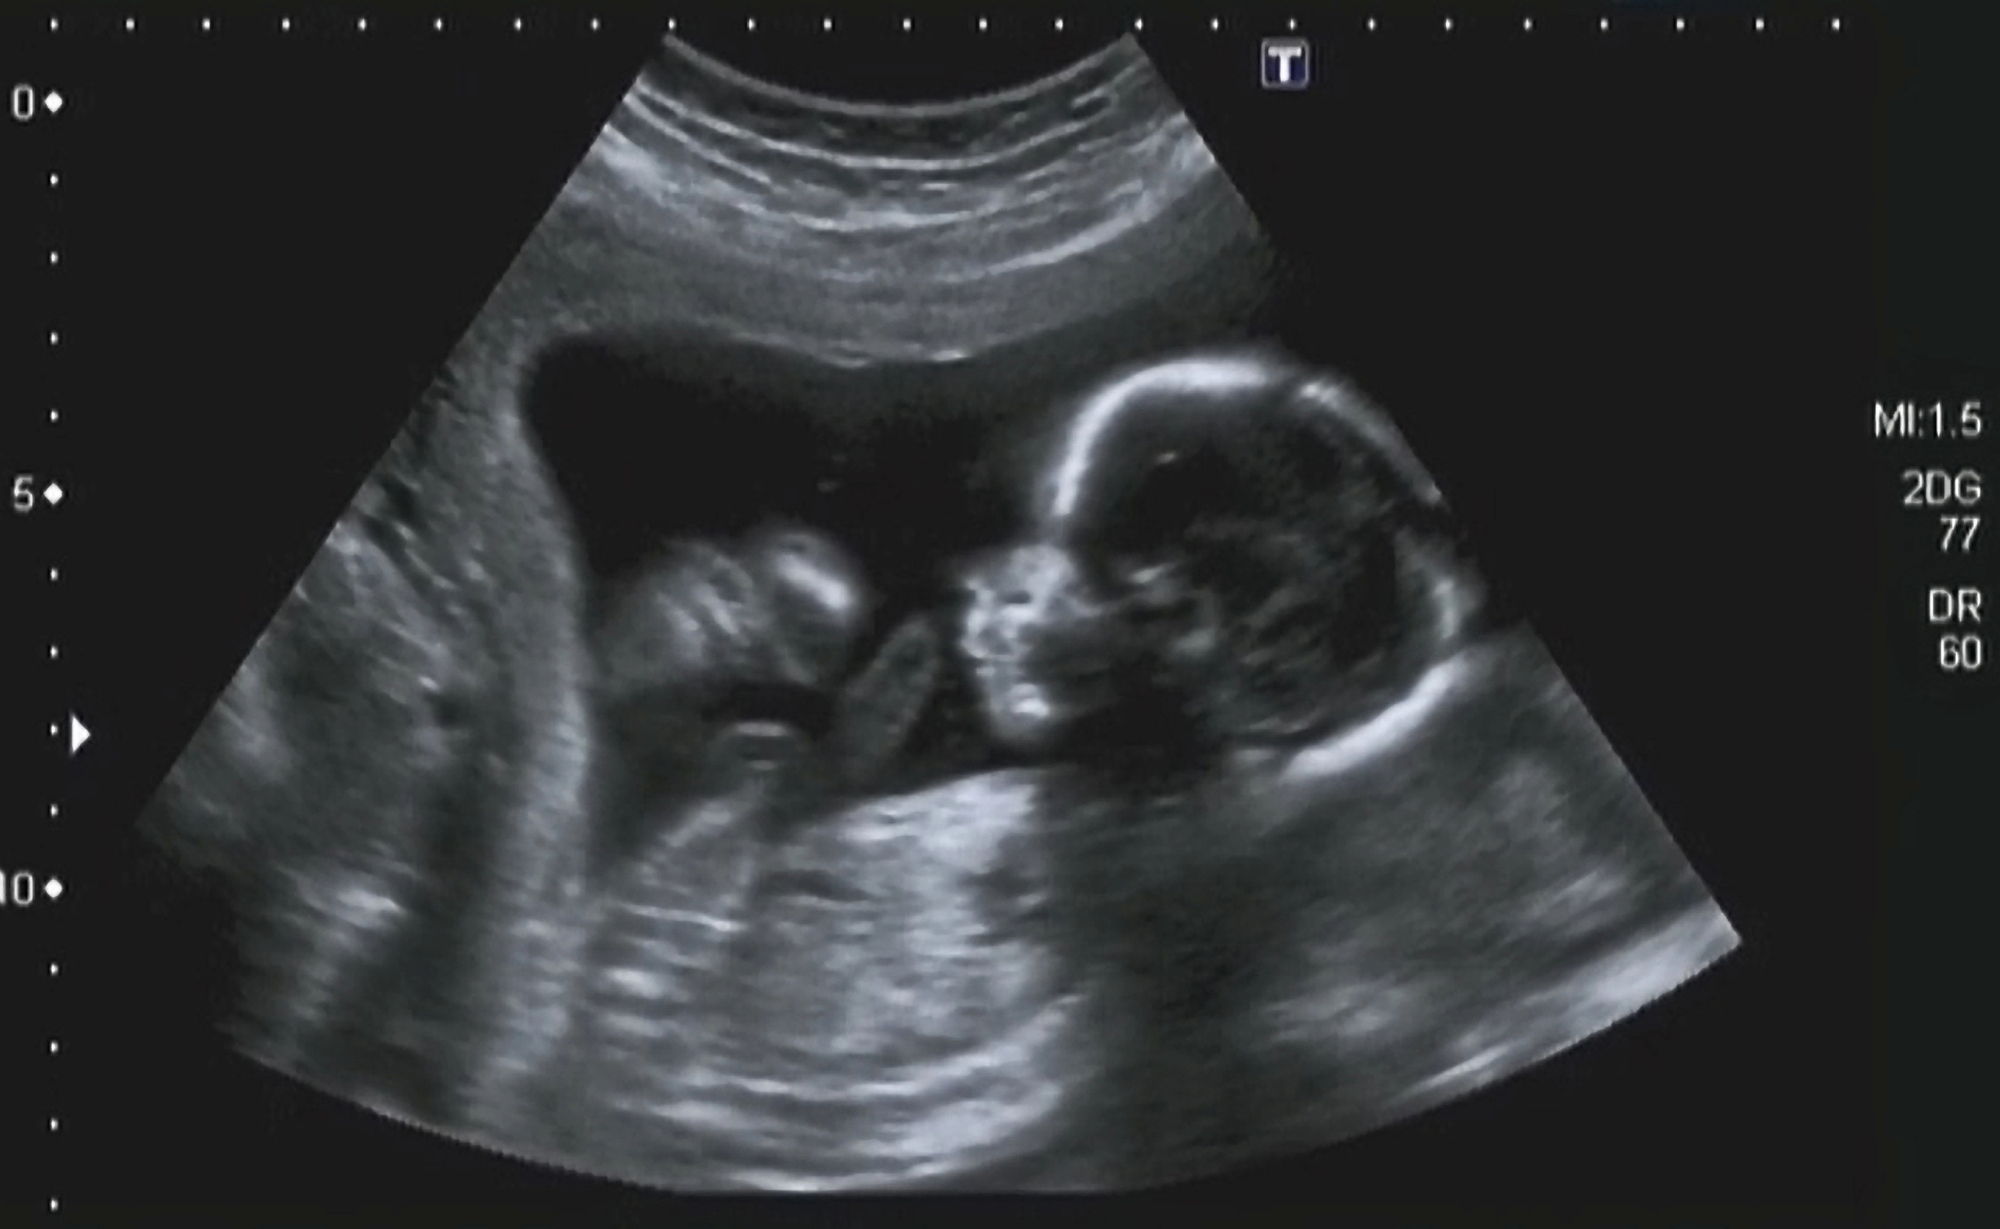

Polihidramnij (lat. Polyhydramnion) – POVEĆANA KOLIČINA PLODOVE VODE, je pojam koji označava količinu plodove vode veću od 2000 ml. Otkriva se ultrazvukom i to određivanjem indeksa plodove vode (engl. AFI-amniotic fluid indeks) koji se provodi između 36. i 42. tjedna trudnoće. Ultrazvukom se mjere okomiti džepovi plodove vode u četiri kvadranta, mjere se zbrajaju te se dobije AFI. Izrađene su tablice, količine plodove vode u odnosu na tjedne trudnoće, tako da se situacija s količinom plodne vode može precizno pratiti. Polihidramnij se dijagnosticira kada je indeks plodne vod veći od 24.

Kako se podova voda stvara, tako se i resorbira (razgradnja tvari i upijanje). Najčešći uzroci veće količine plodove vode su fetalne malformacije. Malformacija (lat.) je defekt organa ili većeg dijela tijela u embrionalnom razvoju koji nastaje prije završetka razvoja organa. Kod takvih malformacija stvaranje plodove vode je uredno, no nedostaje resorpcija plodove vode. Takvim načinom je onemogućena i sama cirkulacija plodove, te se ona nagomilava.